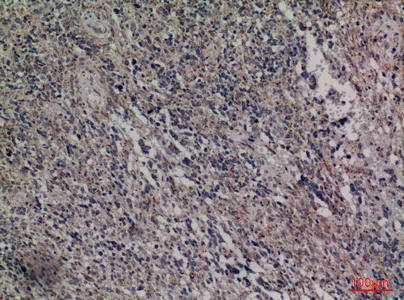

TH Rabbit Polyclonal Antibody

Cat: APRab18871

Size1:50μl Price1:$118

Size2:100μl Price2:$220

Size3:500μl Price3:$980

Size2:100μl Price2:$220

Size3:500μl Price3:$980